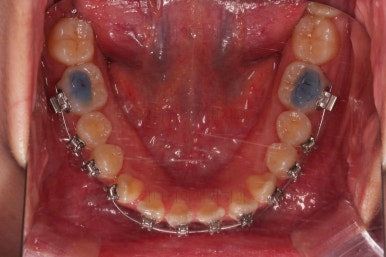

초진 시 입안의 모습입니다.

치열이 많이 삐뚠 것은 아니지만 앞니쪽이 삐뚤어 있고요. 아랫니 사이사이에 고루 틈새가 있네요.

윗니는 삐뚤고(공간부족), 아랫니는 틈새가 있다면(공간 과잉) 그 부조화는 부정교합을 의미합니다.

어금니 교합이 전반적으로 아랫니가 뒤로 빠져있는 교합이어서 맞물림이 좋지 못한 상태였어요.